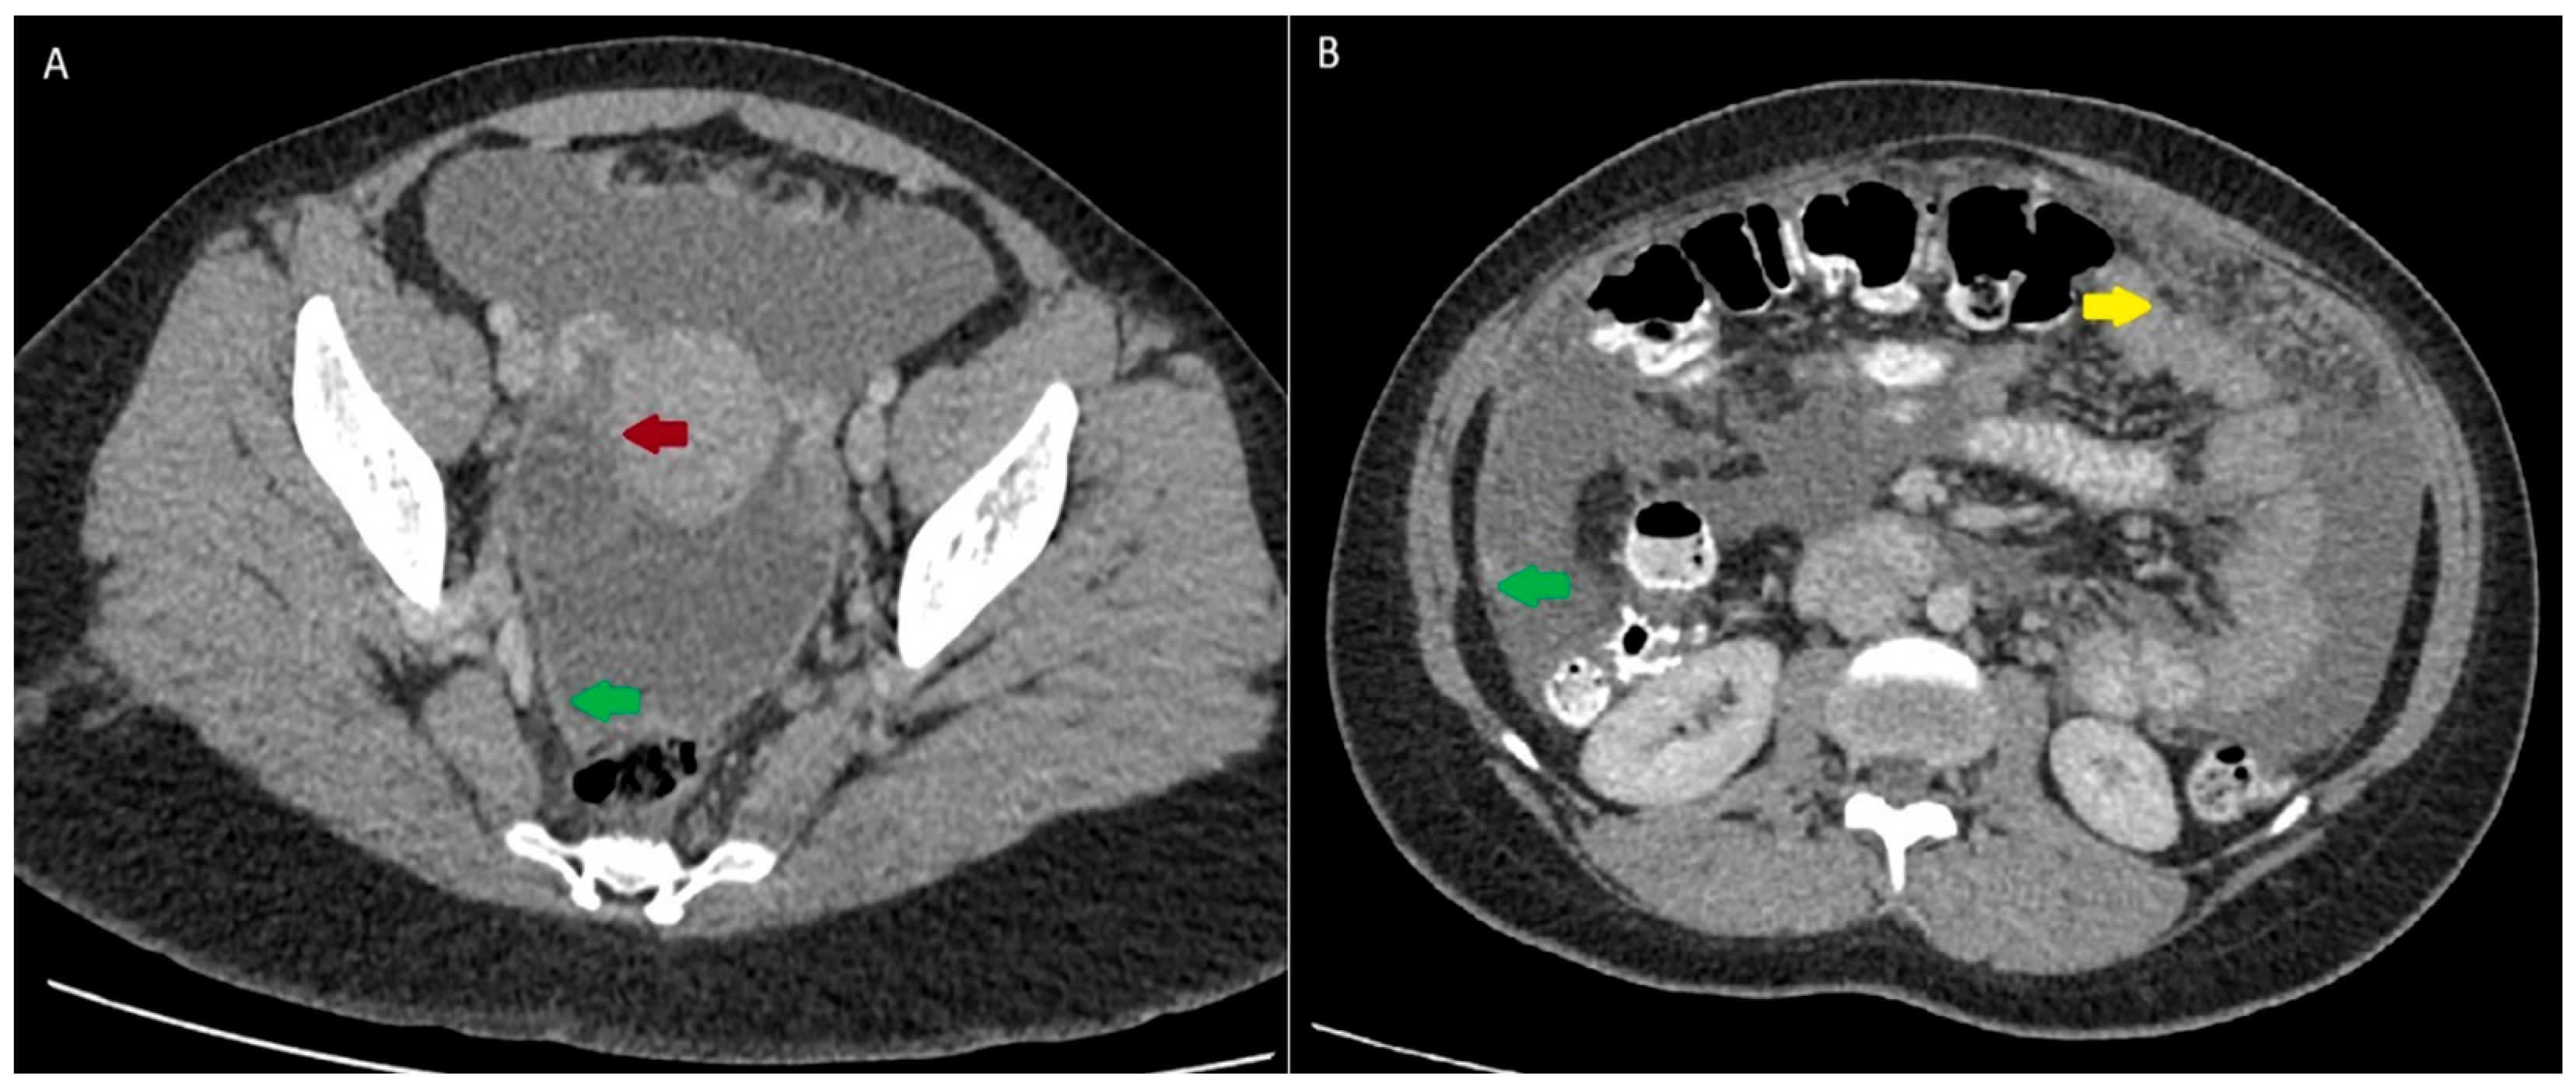

2. Case Presentation